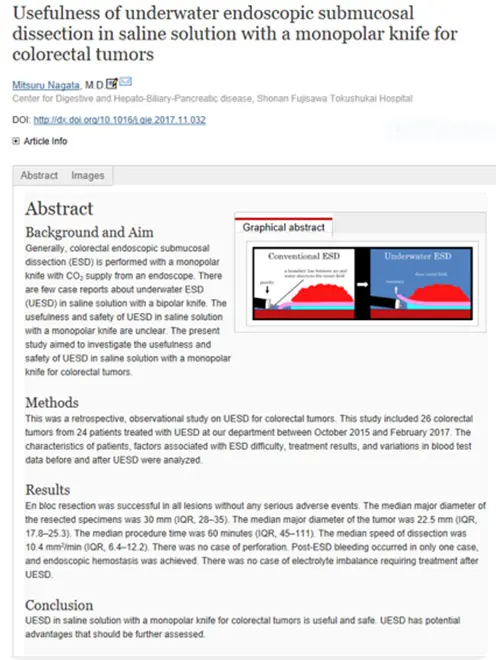

生理食塩水の中で行うESDです。水中では光の反射による視野障害がなくなり、自然な拡大効果もかかるため、鮮明な視野が得られます。

ケースバイケースで従来のESDと使い分けています。

この方法は2018年に当科が原著形式の英語論文として発表し、消化器内視鏡のトップジャーナルであるGastrointestinal Endoscopy(GIE)に掲載されました。

全国的にもまだ出来る病院が少ない十二指腸ESDを提示します。十二指腸ESDではUnderwater ESD(生理食塩水の中で行うESD)が有効です。